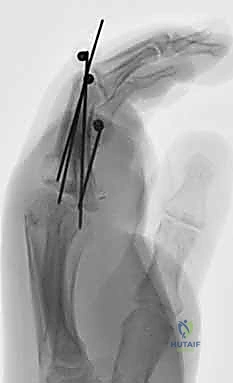

الأساس المتين هو أول خطوة في البناء. يقوم الدكتور هطيف بتقصير العظام قليلاً (Bone Shortening) لتخفيف الشد على الأوعية الدموية والأعصاب عند توصيلها. يتم تثبيت العظام باستخدام أسلاك كيرشنر المعدنية (K-wires)، أو مسامير دقيقة، أو صفائح معدنية صغيرة. التثبيت يجب أن يكون قوياً ليسمح ببدء العلاج الطبيعي المبكر.